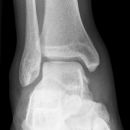

Sprunggelenk